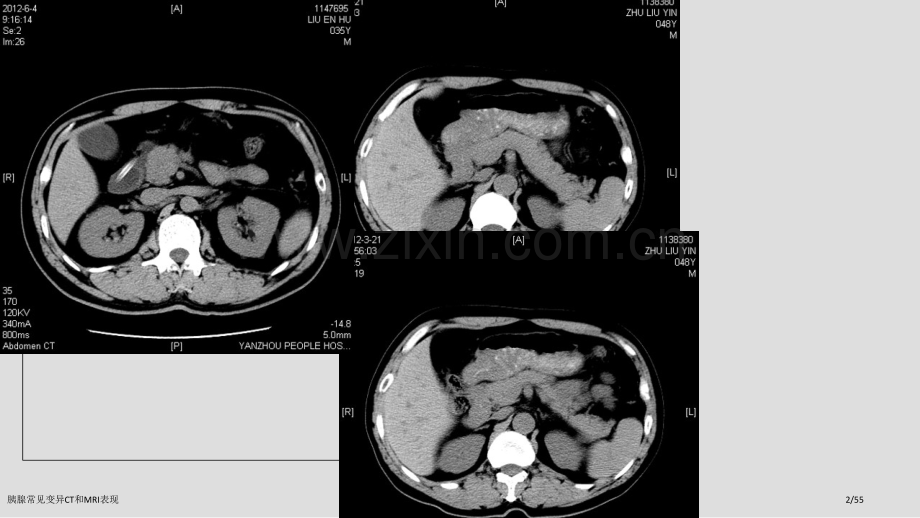

胰腺常见变异CT和MRI表现1/55胰腺常见变异CT和MRI表现2/55胰腺常见变异CT和MRI表现3/551、胰腺形态变异 胰头异常 胰颈异常突起 胰尾增宽 胰尾缺如 环状胰腺 分叉胰腺 胰腺扭曲 胰周脂肪嵌入?右位胰腺 2、胰腺位置变异 异位于肾上腺区3、胆管、胰管变异 胆囊管低位汇入胆总管4、胰腺血管变异 胰腺血管海绵样变5、胰周肠管 误为胰腺肿瘤胰腺常见变异CT和MRI表现4/55先天变异先天变异胰腺解剖变异可分为融合异常(胰腺分裂)、移行异常(环状胰腺、异位胰腺)及重复异常(数目或形态异常)。胰腺融合或移行异常可引发一些使一些胰腺或胰周疾病发生率增加解剖变异。胰腺常见变异CT和MRI表现5/55胰腺分裂胰腺分裂胰腺分裂是因为背侧与腹侧芽孢融合失败所致。腹侧导管(Wirsung导管)只引流腹胰,而大部分胰液经过背侧导管(Santorini导管)引流至小乳头。这是最常见胰腺先天变异,尸检人群中占4-14%;ERCP中约占3-8%;MRCP中约9%。大多数情况下,背侧及腹侧胰管并不交通,但在部分个体,它们之间有细小管道交通,而在另外一些人群,腹侧胰管完全缺如。尽管仍存在争议,还是认为胰腺分裂与急性及复发性胰腺炎相关。据报道,在胰腺完全分裂人群中,发生急性胰腺炎者占25%-38%。胰腺分裂主要解剖特点,即背胰导管与Santorini导管相连续并引流进小乳头,这已在ERCP和MRCP上证实。腹胰导管引流入大乳头且与背胰导管不相交通。胰腺常见变异CT和MRI表现6/55胰腺常见变异CT和MRI表现7/55图:岁男性胰腺分裂患者图像,示主胰管(直箭)单独引流入小乳头(虚箭),而胆总管(箭头)与小腹侧导管(弯箭)汇合后在下方层面经过大乳头引流入十二指肠。胰腺常见变异CT和MRI表现8/55环状胰腺环状胰腺环状胰腺是一个少见先天变异,因腹胰不完全旋转造成部分胰腺围绕十二指肠降部而形成环状胰腺分两型:壁外型及壁内型。在壁外型,腹胰导管包绕十二指肠后汇合到主胰管。而壁内型,胰腺组织与十二指肠壁肌纤维混合,其小胰管直接引流入十二指肠。壁外型环状胰腺患者,其临床表现为高位胃肠道梗阻。而壁内型患者表现为十二指肠溃疡。壁外型需手术治疗,普通行旁路搭桥手术;合并十二指肠溃疡壁内型患者,普通选择胃大部切除术,合并或不合并迷走神经离断术。环状胰腺儿童患者可在传统腹部平片表现为经典双泡征,较大近侧气泡为扩张胃,而较小远侧气泡则是扩张十二指肠球。钡餐检验表现为壶腹周围不足梗阻,十二指肠降部可见外压性偏心性充盈缺损 胰腺常见变异CT和MRI表现9/55图:环状胰腺图。腹胰(箭头)包绕十二指肠降部,腹胰导管(箭)绕过十二直肠后与背侧导管相融合,形成Wirsung导管并引流入大乳头 胰腺常见变异CT和MRI表现10/55图:年轻女性环状胰腺患者上消化道片,可见裂隙状、光滑狭窄十二指肠降部(箭)。无胃扩张或机械性梗阻存在。对比剂顺利进入十二指肠及近段空肠。胰腺常见变异CT和MRI表现11/55图:岁男性环状胰腺患者增强,可见包绕着塌陷十二指肠正常强化胰腺组织(箭)。患者喝水作为口服阴性造影剂。腹胰导管(箭头)引流入十二指肠。胰腺常见变异CT和MRI表现12/55环状胰腺胰腺常见变异CT和MRI表现13/5543岁环状胰腺患者,有胰尾部胰高血糖素瘤切除史。胰腺组织包绕充满造影剂十二指肠降部(箭),使这一变异在即使没有静脉注射对比剂情况下也很好辨识。胰腺常见变异CT和MRI表现14/55胰腺不发育非常少见且基本不能存活,发育不全则表现为腹侧原基或背侧原基缺如。背胰部分不发育较腹胰不发育更常见,但背胰完全不发育非常罕见。在影像学上,背胰发育不全表现为临近十二指肠短而圆胰头,胰颈、体、尾缺如(图11)。胰腺发育不全可能与胰腺炎及多脾综合征发病率上升相关。胰腺不发育或发育不全胰腺不发育或发育不全胰腺常见变异CT和MRI表现15/55胰腺常见变异CT和MRI表现16/55胰尾缺如,多脾综合征(186253,F47)胰腺常见变异CT和MRI表现17/55异位胰腺异位胰腺又称为迷走胰腺或副胰腺,是正常胰腺解剖部位以外孤立胰腺组织,和正常胰腺之间无任何解剖、血管关系,属于一个先天畸形。可能发生在消化道或消化道以外任何部位。异位胰腺也能够产生分泌各种胰酶和胰液,也能够发生急性、慢性胰腺炎甚至囊肿、肿瘤等正常胰腺可发生任何病变。胰腺常见变异CT和MRI表现18/55异位胰腺异位胰腺异位胰腺常见于胃窦粘膜下(30%)、十二指肠近侧部分(30%)、十二指肠其它部位(20%)及小肠其它部位(20%)。异位胰腺包含正常胰腺组织,常包含胰岛细胞及小胰管,其在上消化道钡餐检验中表现为有中央钡龛或脐凹小圆形肿块.脐凹代表异位胰腺原始导管开口。假如缺乏这种征象,则在影像学上就难以与其它粘膜下肿瘤判别,如十二指肠腺瘤、平滑肌瘤或淋巴瘤。异位胰腺是功效性,也与正常胰腺一样易患炎性或肿瘤性疾病,但大多数是无症状而偶然发觉。囊性萎缩是其严重但少见并发症,表现为异位胰腺内导管扩张,常见于十二指肠降部。常认为与小胰管阻塞而重复发生胰腺炎相关。其影像特征为增厚十二指肠壁内包含多个中、重度强化囊腔。二分之一患者可见邻近炎性改变,有或无淋巴结肿大。囊性萎缩是十二指肠异位胰腺其中一个良性改变,其它还包含胰腺错构瘤、十二指肠壁旁囊肿及沟槽部胰腺炎,也称为十二指肠旁胰腺炎。总来说,其可造成十二指肠壁增厚,壁内包含扩张导管及假囊肿、十二指肠腺增生或其内间隔圆形小叶状胰腺组织黏液组织增生。胰腺常见变异CT和MRI表现19/55异位胰腺(217449,M46):胃部不适就诊。胰腺异位于12指肠前外侧,与胰颈分离,平扫及增强扫描,与胰腺主体同时改变。胰腺常见变异CT和MRI表现20/55胰尾异位于肾上腺(189101,F58)胰腺常见变异CT和MRI表现21/55胰尾异位于肾上腺(96394,11412,M51)胰腺常见变异CT和MRI表现22/55胰尾异位于肾上腺(96394,11412,M51)胰腺常见变异CT和MRI表现23/55继发性胰腺位置异常(198008,M61):左肾癌术后,先天性脾缺如。胰腺常见变异CT和MRI表现24/55 右位胰腺(84413,F46):全内脏转位。胰腺常见变异CT和MRI表现25/55胰 管 变 异胰管位于胰实质内,分为主胰管和副胰管,主胰管起自胰尾,横贯胰全长,沿途收纳许多小叶间导管。主胰管抵达胰头右侧时,通常与胆总管汇合壶腹部而开口于十二指肠大乳头胰管与胆总管开口,通常有以下情况(1)胰管与胆总管完全分开,分别开口于十二指肠(3.1%)。(2)胰管与胆总管平行,分别开口于同一乳头(50%)(3)胰管与胆总管汇合成Vater壶腹后,再共同开口于十二指肠大乳头(46.9%)副胰管短而细,居胰头上部内,主要引流胰头上部和侧腹部,一端与主胰管联络,一端开口于十二指肠小乳头。胰腺常见变异CT和MRI表现26/55胰腺常见变异CT和MRI表现27/55胰腺常见变异CT和MRI表现28/55胰腺常见变异CT和MRI表现29/55球形胰头(239537,M62):误为胰头癌而手术。胰腺常见变异CT和MRI表现30/55胰腺头部异常饱满(198556,F45):因“中毒性肝炎”就诊。胰腺常见变异CT和MRI表现31/55胰腺颈部异常突起(193730,M42),041108胰腺颈部异常突起(193730,M42),040609胰腺常见变异CT和MRI表现32/55胰腺变异(213580,M71):体检发觉肾囊肿就诊。胰腺常见变异CT和MRI表现33/55胰腺头部异常突起(96372,M41)胰腺常见变异CT和MRI表现34/55胰尾增宽(147617)胰腺常见变异CT和MRI表现35/55胰腺尾部异常增宽(199275,F50):体检就诊。胰腺常见变异CT和MRI表现36/55胰腺变异(212572,M38):因重复尿黄就诊。胰腺常见变异CT和MRI表现37/55胰尾变异(213212,M48):体检诊疗“胰腺占位”。胰腺常见变异CT和MRI表现38/55胰尾分叉胰腺常见变异CT和MRI表现39/55胰腺常见变异CT和MRI表现40/55胰腺常见变异CT和MRI表现41/55胰腺常见变异CT和MRI表现42/55胰周脂肪嵌入(103335,M45):因血管瘤就诊。胰腺常见变异CT和MRI表现43/55胰周脂肪嵌入(198061,M31):多囊肾。胰腺常见变异CT和MRI表现44/55胰腺扭曲似断裂(183785,M76)胰腺常见变异CT和MRI表现45/55脾静脉海绵样变(207175,M46):慢重肝就诊,脾肾分流术后。胰腺常见变异CT和MRI表现46/55动态改变(204986,F42):充分饮水(左)胰头形态不规则,空腹(右,隔1天)胰头呈三角形。胰腺常见变异CT和MRI表现47/55胰尾截断(221535,F40):上腹不适,CA19-9显著升高。胰腺常见变异CT和MRI表现48/55胰尾受肾囊肿挤压变形(222444,F35):体检发觉肾囊肿就诊。胰腺常见变异CT和MRI表现49/55胰腺常见变异CT和MRI表现50/55胰腺常见变异CT和MRI表现51/55胰旁肠管(199513,M47):以HCC就诊,“病变”与邻近肠管相通,邻近有正常胰腺。胰腺常见变异CT和MRI表现52/55胰周肠管切末误为肿瘤胰腺常见变异CT和MRI表现53/55胰腺脂肪替换(193877,M62):胃癌就诊。胰腺常见变异CT和MRI表现54/55胰腺常见变异CT和MRI表现55/55